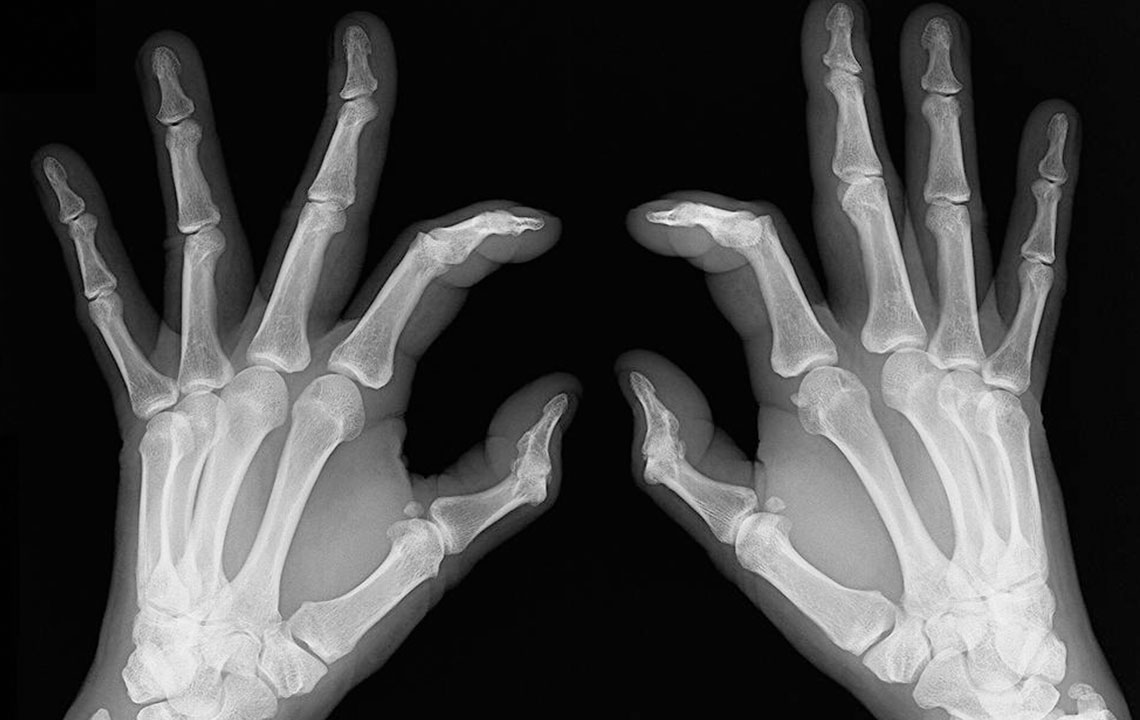

Early signs of rheumatoid arthritis and how to catch them

- Bone deformation: Arthritis also attacks the bones and makes them crooked and stiff. Look out for signs of any subtle changes in your joints and test them for pain levels.